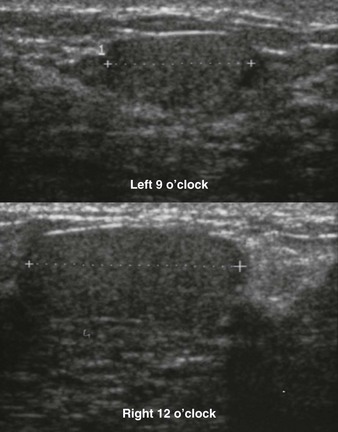

Metastatic lesions in the breast are usually a late finding of malignancy. They typically present as multiple round bilateral breast masses (Fig. 11-17), and may also be present in the subcutaneous tissues of the axilla. The mass margins are usually ill-defined compared with those of multiple cysts or fibroadenomas. Metastasis can also present as axillary or intramammary adenopathy (Fig. 11-18).

FIGURE 11-18 Metastatic Intramammary Lymph Node.

Although the mammographic appearance is nonspecific, the location and US appearance are consistent with an abnormal intramammary lymph node. Diagnosis: metastatic melanoma.

Non-Hodgkin lymphoma (NHL) rarely involves the breast. Breast involvement usually occurs in women with known extramammary disease. NHL of the breast most commonly presents as a solitary mass, and multiple masses are less common. Primary breast lymphoma is very rare (Fig. 11-19).

FIGURE 11-19 Primary Breast Lymphoma.

A middle-aged woman presents with a palpable retroareolar mass. Mammography shows an obscured mass that is markedly hypoechoic and vascular by US. Core biopsy revealed non-Hodgkin lymphoma (diffuse large B cell). There was no evidence of extramammary disease and the patient was treated with chemotherapy and radiation therapy.

Rhabdomysarcoma and leukemic infiltrates can present as palpable thickening with asymmetry on mammography and poorly defined areas of hyperechogenic breast tissue on US (Fig. 11-20). Fat necrosis differs in appearance; it is typically subcutaneous and better defined.

FIGURE 11-20 Leukemia of the Breast.

A 28-year-old woman with bilateral palpable breast masses. The mammogram shows bilateral irregular masses. On US, the palpable lumps correspond to areas where the echotexture is very heterogeneous. In some regions, the finding is very hyperechoic. The patient has a history of leukemia, thought to be in remission. Unfortunately, this represents recurrence.